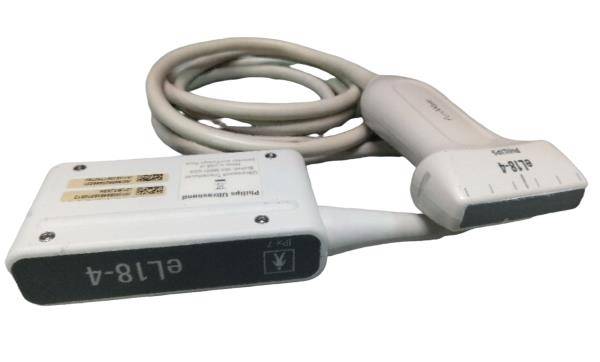

The Laptop Color Doppler Ultrasound is an innovative diagnostic machine designed for clear and precise imaging. It boasts advanced features, making it an indispensable tool for medical professionals. Whether you're in a hospital setting or a small clinic, this portable ultrasound scanner provides accurate diagnostics without compromising on quality.

The user interface of the Laptop Color Doppler Ultrasound is designed for ease of use. It features a high-resolution display, intuitive controls, and customizable settings. This makes it accessible for both new and experienced Sonographers. The device runs on powerful software that supports various diagnostic applications, ensuring versatility in its use. Therefore, it can be used for a wide range of procedures, from obstetric exams to cardiac assessments.